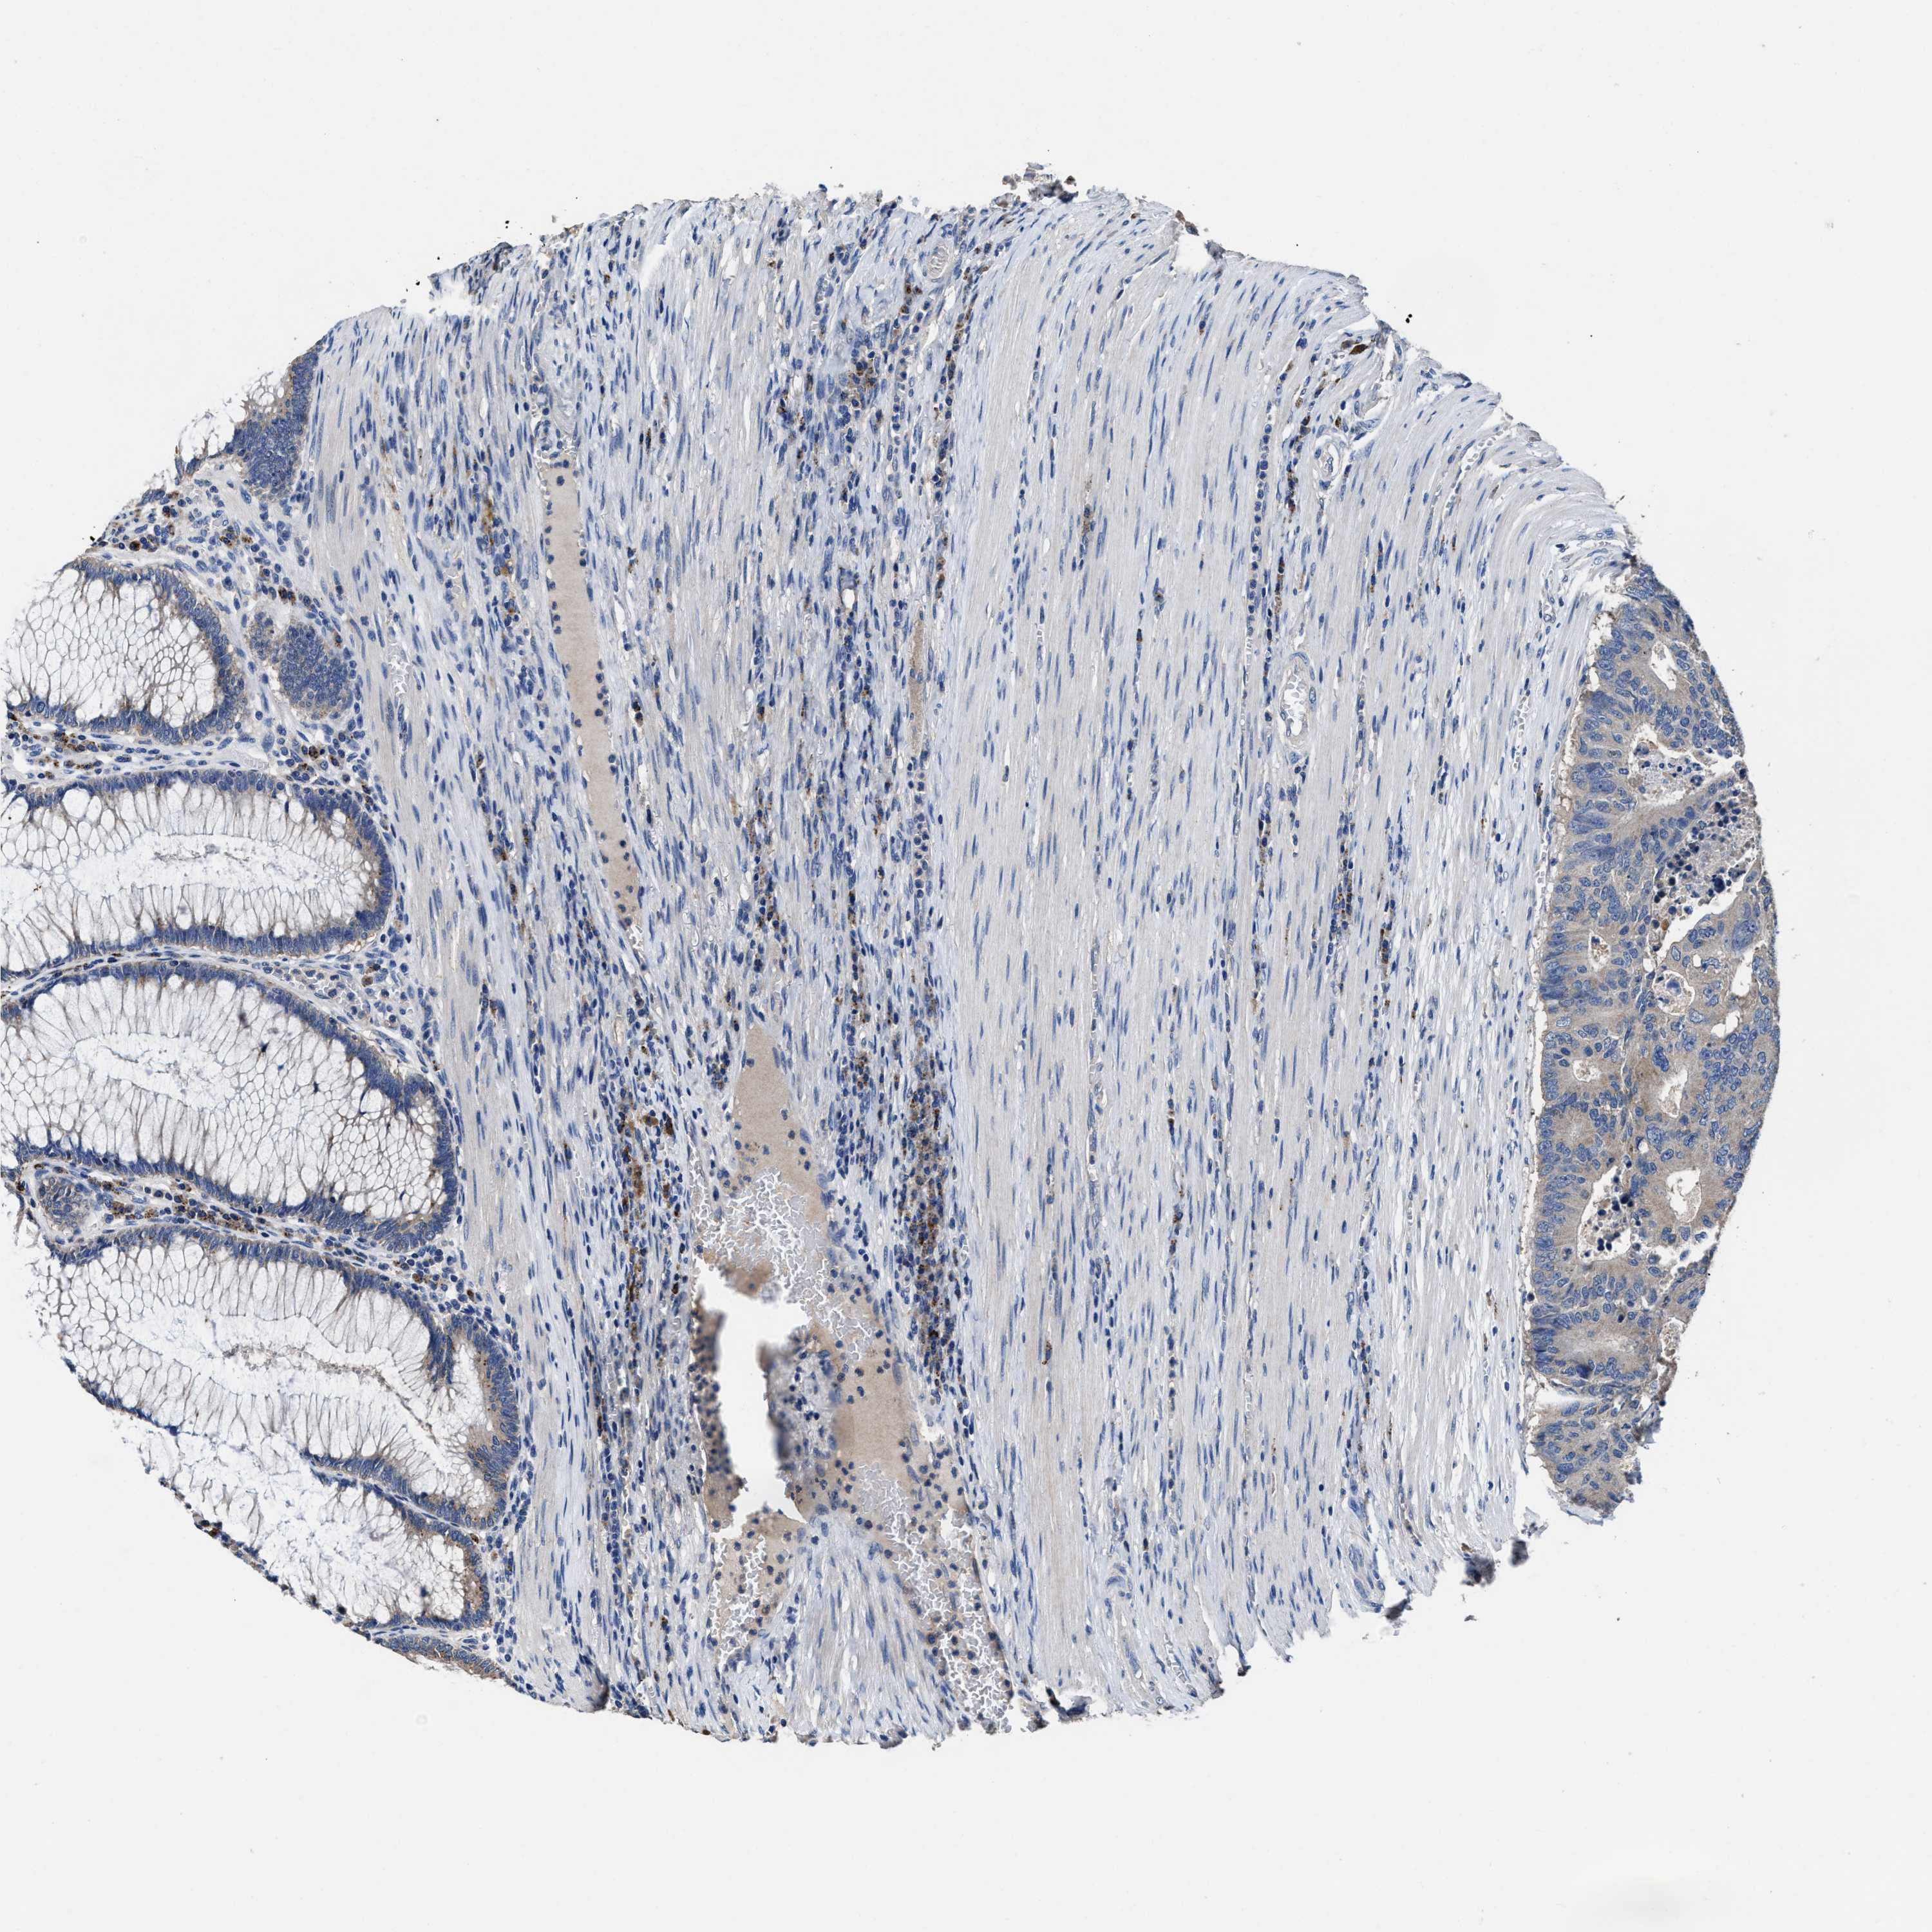

CANCER COLORECTAL CANCER Show tissue menu

Colorectal cancer

Human cancer

Colon adenocarcinoma